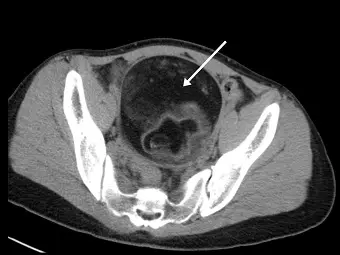

女性患者有卵巢畸胎瘤( ovarian teratoma ),未施打顯影劑的骨盆腔電腦斷層顯示腫瘤內有一低密度區(如下圖箭號處)。經測量其密度約為 -100 HU ,最有可能為下列何者?

這是一張骨盆腔的無顯影劑電腦斷層(non-contrast CT)軸狀切面影像:

- 病灶位置與型態:影像中央可見一巨大的局部不均質腫塊(heterogeneous mass),佔據大部分的骨盆腔。

- 箭號指示處:白色箭號指著腫瘤內部一塊明顯的「低密度區(hypodense area)」。此區域在影像上呈現深灰色,其密度明顯低於周圍軟組織與肌肉,但又比腸道內的氣體(呈現純黑色)來得亮。題目敘述指出此區域測量值約為 -100 HU。

- 伴隨特徵:腫瘤內部下方及邊緣可見較高密度的軟組織結構(可能為羅基坦斯基結節 Rokitansky nodule 或其他胚層組織),為畸胎瘤典型的異質性表現。

- (A) 脂肪:正確。脂肪在 CT 上的標準衰減值(attenuation)約介於 -50 HU 至 -150 HU 之間。題目中測量結果為 -100 HU,完美吻合脂肪的影像特徵。且卵巢畸胎瘤(通常為成熟型皮樣囊腫)最典型的成分即是大量脂肪與皮脂物質。